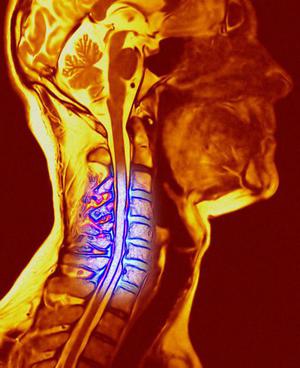

ВСД и шейный остеохондроз

очень часто взаимосвязаны

. Так как при патологии нарушается строение позвоночного столба, то в процессе меняются также сосудистые и нервные ткани, которые вплотную прилегают к позвонкам. При их раздражении возникает спазм артерий, по этой причине к тканям мозга поступает меньше необходимых для нормального функционирования веществ. При ишемии нейронов нарушается производство гормонов, необходимых для функционирования нервной системы. Именно тогда ярко проявляются классические симптомы ВСД.

При подозрении на ВСД специалист назначает дополнительные обследования для более точной диагностики. При сочетании с шейным остеохондрозом, сосудистая дистония часто сопровождается и другими признаками патологии работы нервной системы. Важное место при диагностике отводится УЗГД сосудов шеи. Во время этой процедуры очень часто выявляется синдром позвоночной артерии, что тоже может быть симптомом. Эта патология сопровождает остеохондроз и связана с сосудистым спазмом. Эти сосуды находятся в непосредственной близости от позвоночных отростков и именно по ним кровь направляется в мозг. При спазме кровь перестает поступать в достаточном количестве, нарушается работа мозга и нервной системы.